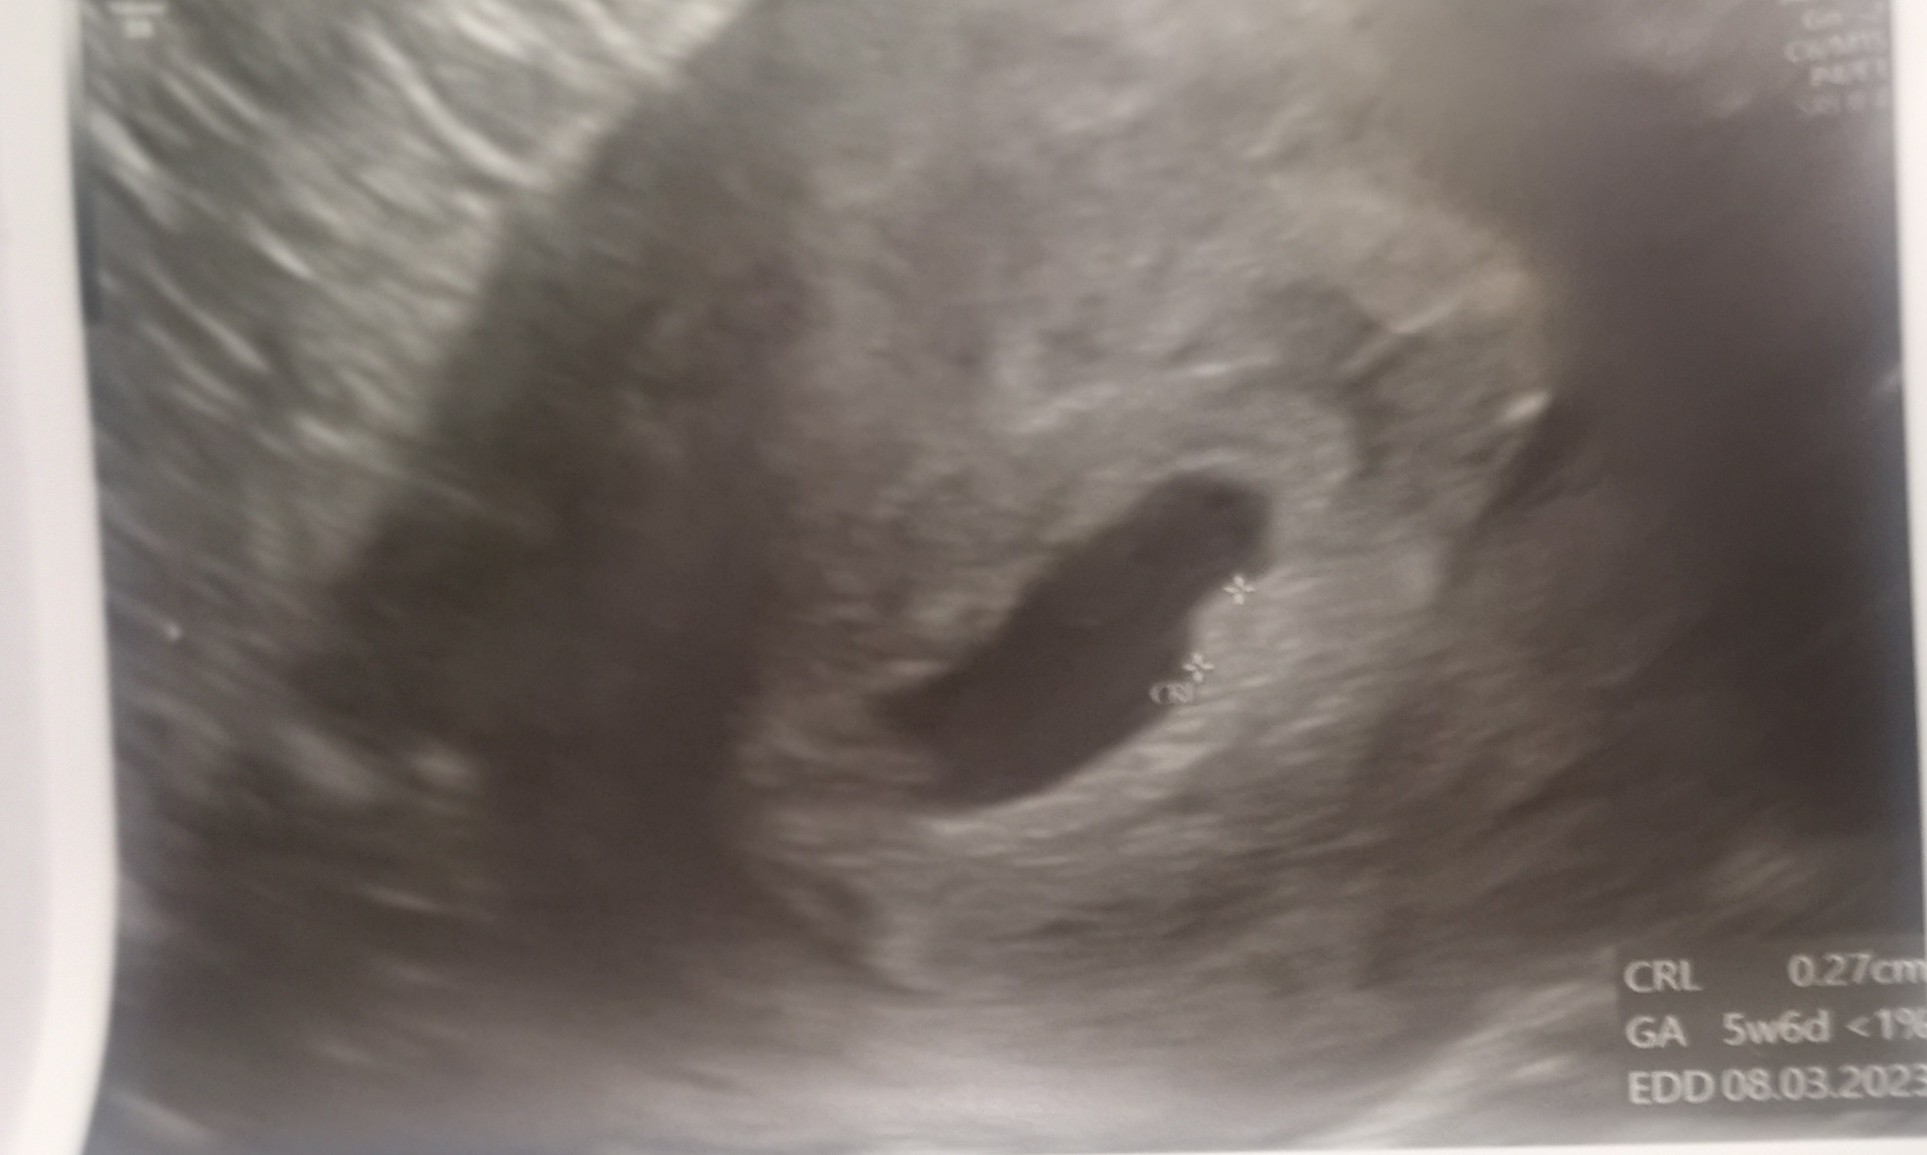

Wszystko jest ok! Ciąża 5+6. W macicy. Nic złego na tym etapie się nie dzieje! Beta ok. Progesteron ok. Ulżyło mi. To było najlepiej wydane 300 zl.![]()